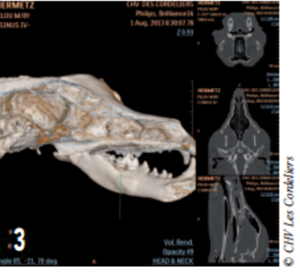

Le scanner a révélé la présence d’une lyse osseuse de l’os alvéolaire mandibulaire s’étendant de la racine dorsale de la carnassière jusqu’à la racine caudale de la deuxième prémolaire (photos 2 à 6).

Photo 3 : Reconstruction en 3D montrant la lyse osseuse de la mandibule s’étendant de la carnassière à la deuxième molaire.